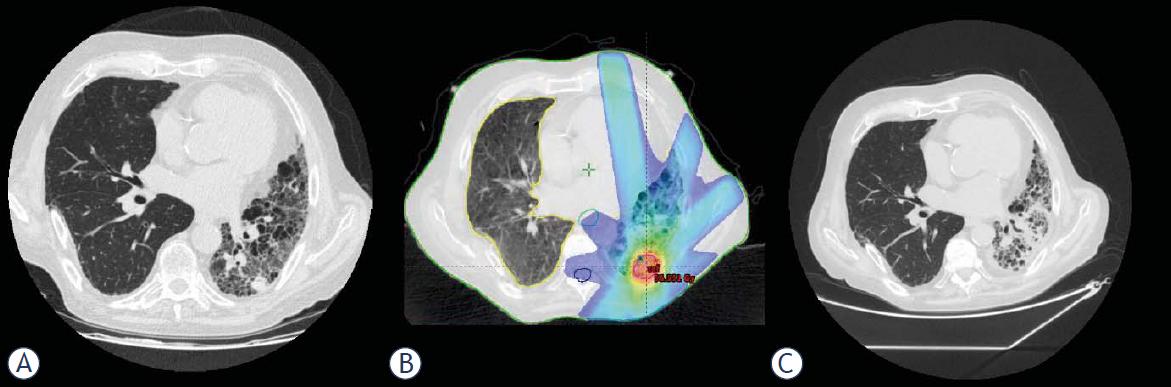

A 72-year-old man with a history of hypertension, diabetes mellitus type 2, chronic renal failure and ischemic heart disease. Underwent right lung transplant in 2002 due to IPF, and was treated with tacrolimus and mycophenolic acid to prevent rejection. In 2013 a nodule was detected in the left lower lobe and increased in size to 15 mm in October 2013. There was no FDG uptake in the nodule. The patient was discussed in a multidisciplinary tumor board and it was decided to treat the lesion with SBRT without histological confirmation. The patient was treated in February 2012 to a dose of 54 Gy in three 18 Gy fractions. Treatment was well tolerated with no adverse events or measurable toxicity. The post SBRT, CT scans yielded a disappearance of the treated nodule (Figure 2). The patient passed away in October 2015 secondary to bacteremia and sepsis.

(A) Pretreatment CT demonstrating a central nodule in the right lower lobe (B) Radiation field arrangement and dose color wash for SBRT (C) CT 2 months after treatment completion demonstrating a complete disappearance of the target nodule.

(A) Pretreatment CT demonstrating a nodule was detected in the left lower lobe (B) Radiation field arrangement and dose color wash for SBRT (C) CT 2 months after treatment completion demonstrating a complete disappearance of the target nodule.